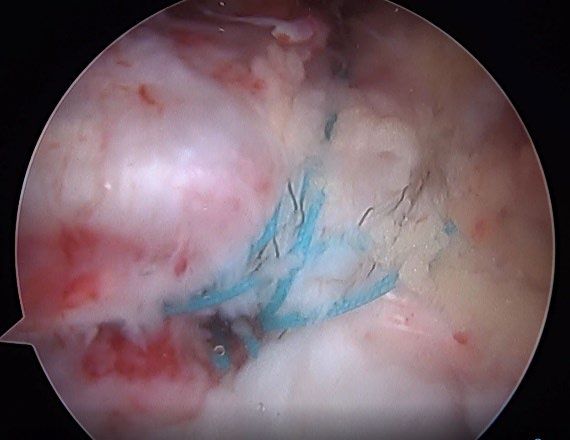

- Proximal Hamstring Tear

Hip conditions often improve with conservative treatment including a short course of rest, anti-inflammatory pain medication, and physical therapy. An ultrasound-guided cortisone injection is sometimes necessary for patients with persistent pain. If pain continues despite conservative treatment, hip arthroscopy is an excellent treatment option for patients with labral tears, femoroacetabular impingement (FAI), tears of the gluteus medius or proximal hamstring, among other conditions.